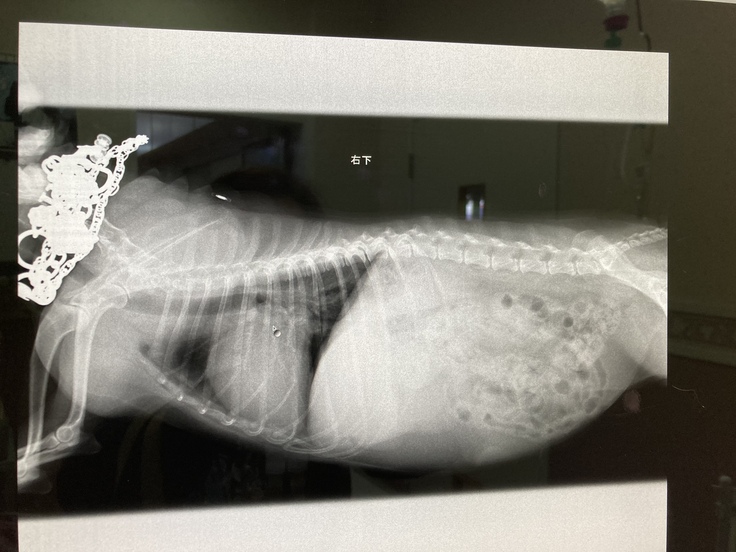

アニーの結石の大きさです。

アニーは診断書通り手術をしなくてはならない事は決定しておりますが、手術予定日は、頑張って資金を貯めてからいつにするかは相談しましょうと、病院から言われています為とにかく 猶予はない! 状態ですが手術費用の目処が立たなければどうしようも出来ない状態です。...